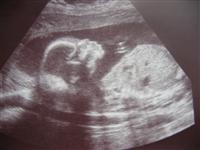

Back from my 20 Wk Ultrasound....

I'm resizing pics as I type...but I'm happy to report we are right on target with how far along I am and how big she is. They think she weighs about 10 ounces.

We reconfirmed that she is a girl and SO NOT SHY about it

She sucked her thumb, had the hiccups, and even flipped from face up to face down. We saw all sorts of different parts of her body which was amazing.

Image Attachment(s):

Shana, little Alyson looks just amazing in those pics!

The pictures are great! I love the first one. Glad to hear that everything went well.